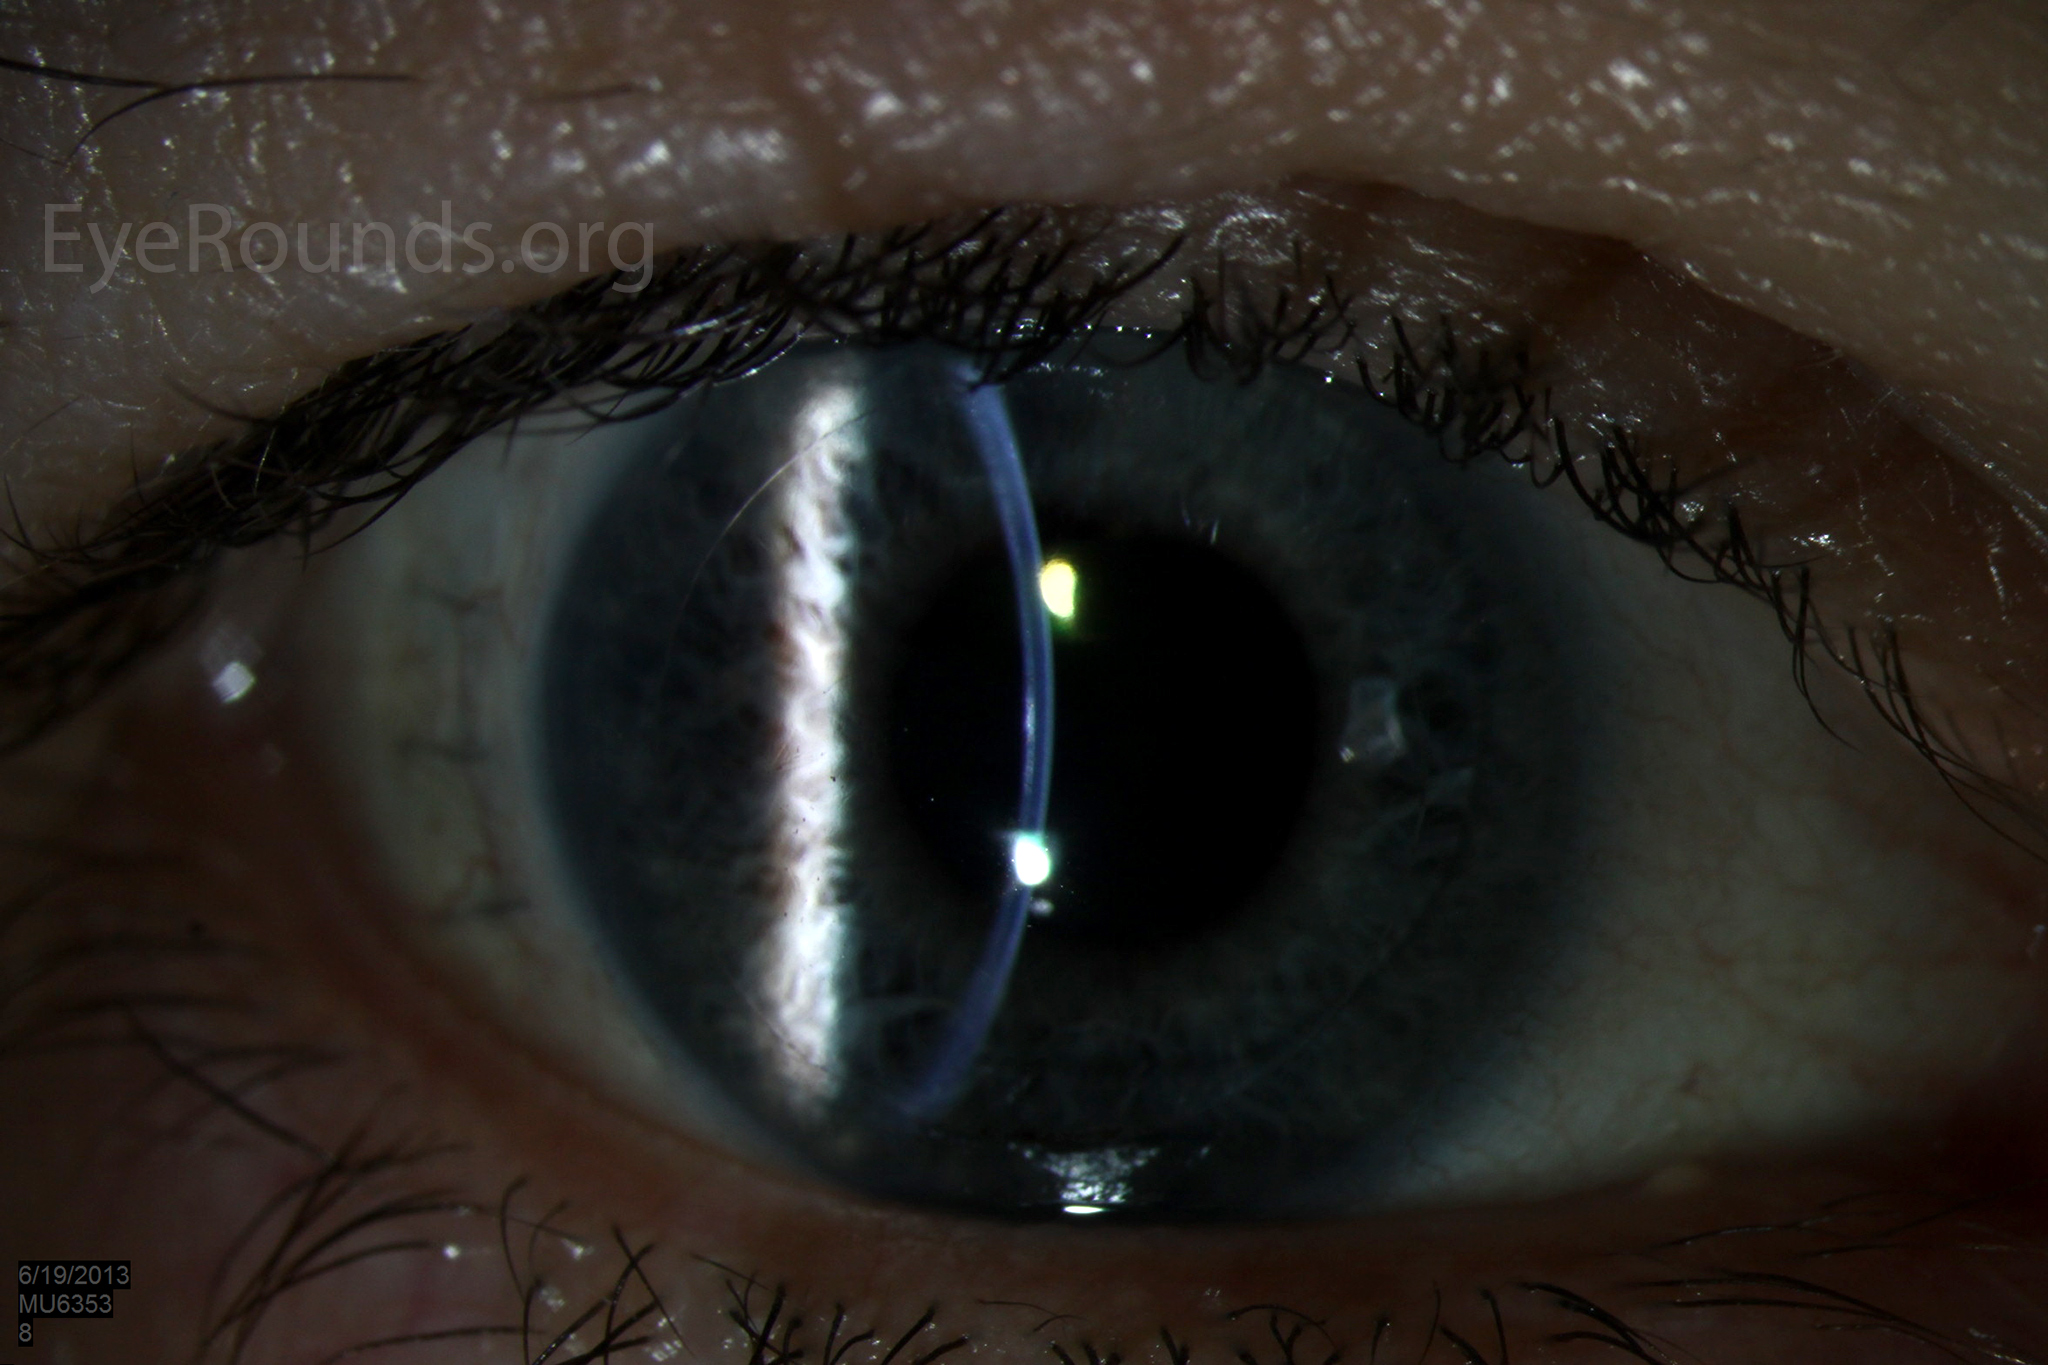

Video Links ArticlesDSAEK is a partial thickness cornea transplant procedure that involves selective removal of the patient's Descemet membrane and endothelium, followed by transplantation of donor corneal endothelium in addition to donor corneal stroma (Figure 8). The transplanted tissue is approximately 100-200 microns thick. If the endothelium of the graft makes contact with any surgical instruments, it will be damaged and the graft may fail; therefore, the surgical procedure is designed to avoid contacting the donor endothelium. A tunneled corneoscleral incision is created, the recipient endothelium and Descemet membrane is removed, the graft is folded and inserted with non-coapting forceps (forceps that do not meet at the tips), and an air bubble is placed in the anterior chamber to support graft adherence. The procedure is used to treat corneal edema in the setting of endothelial dystrophies (such as Fuchs corneal dystrophy and posterior polymorphous corneal dystrophy), pseudophakic bullous keratopathy, iridocorneal endothelial (ICE) syndrome, endothelial failure in the setting of prior intraocular surgery or of a previous PK graft, and other causes of corneal endothelial dysfunction (1, 17-20).

DSAEK offers the advantage of relatively rapid healing time and visual rehabilitation. Compared to PK and DALK, there is less risk of graft rejection and suture-related complications. There is minimal topographic change to the corneal curvature. A somewhat predictable hyperopic shift results (typically 0.8-1.5 D), making intraocular lens selection easier when performing staged or simultaneous cataract surgery.

Postoperative visual acuity can be very good, but there is some limitation from the effects of the stroma-to-stroma graft-host interface. There is also a risk of postoperative graft dislocation.